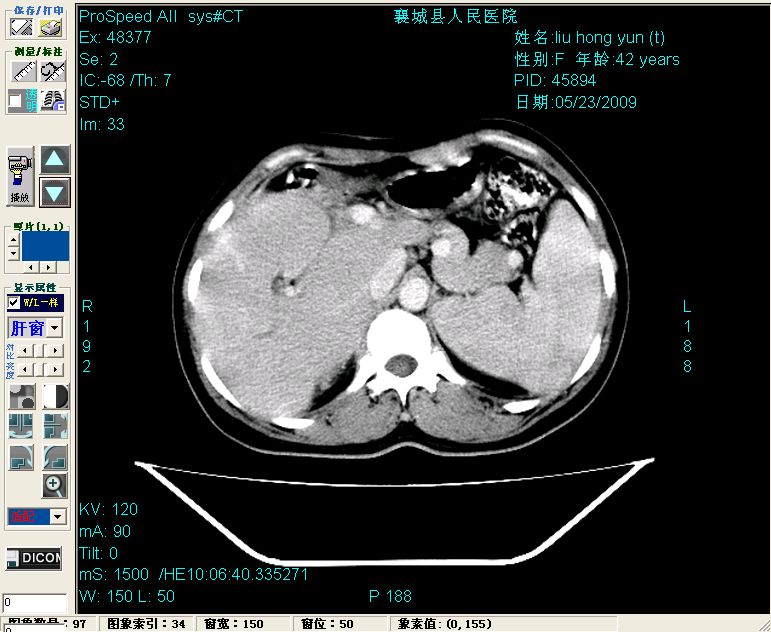

增强:

增强动脉期前述低密度区轻度早其强化,门脉期强化程度显著增高,延期扫描强化程度下降,但仍为相对高密度影

胰头部见结节状高密度影,其前方略可分辨扩强胆部管,平扫到增强始终有,但现在尚难与胃肠造影剂鉴别.

结合病史考虑,1现在引起黄疸体征的原因应该是胆总管胰段结石阻塞,建议局部胃肠造影剂排空后复查.

2左肝及右肝前叶表现考虑胆囊摘除术后所致的肝动门脉瘘形成,慢性纤维组织炎性增生.不完全除外左肝胆管细胞癌

3脾大,可能与动门脉瘘所致门脉高压有关